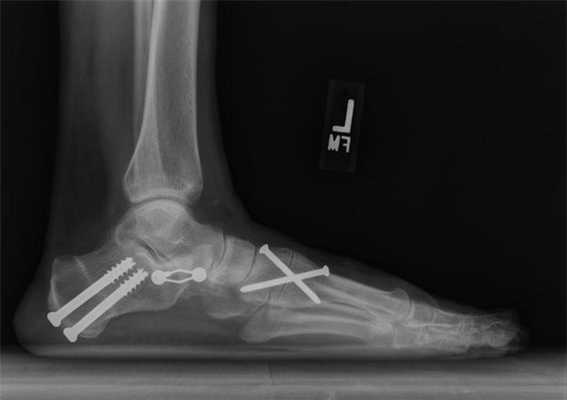

Операцию начинают с послойного рассечения мягких тканей. Получив доступ к нужной кости, хирург распиливает ее. После этого он фиксирует костные фрагменты с помощью систем наружной (аппарат Илизарова) или внутренней фиксации (накостные пластины, винты). Перед ушиванием раны врачи нередко проводят контрольное рентгенологическое исследование. Оно необходимо для подтверждения корректной фиксации кости.

- После остеотомии врачи нередко удаляют металлические имплантаты. Как правило, они делают это спустя 1-2 года. Если фиксация выполнялась аппаратом Илизарова, его снимают намного раньше.